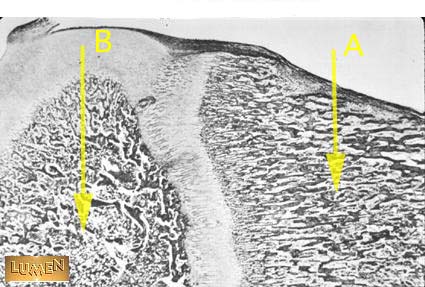

Identify A and B.

Answer A

Primary Ossification Site

Answer B

Secondary Ossification Site